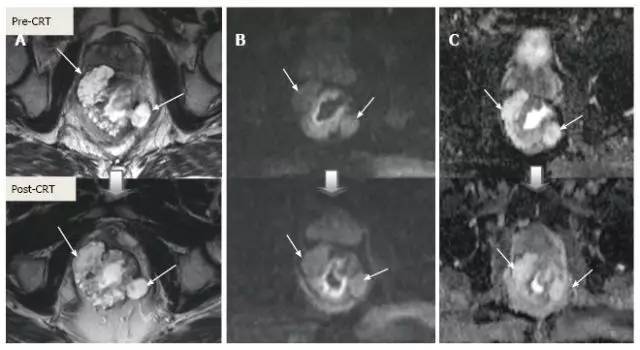

1.T 分期

采用传统 MRI 序列对 CRT 后肿瘤重新分期的精确性差于初始分期,尤其在证实完全缓解(yT0),主要是很难将残留的肿瘤与纤维化、水肿和正常粘膜区分开,因此 CRT 后正常的 2 层直肠壁提示为完全缓解,而残留纤维化既可以是肿瘤残留也可以是完全缓解(图 17)。

实际上 CRT 后 T2 加权 MRI 后上纤维化的信号强度很低,而残留肿瘤区域则为中等强度,仔细评估高分辨图像和 DWI 是能区分小的残留病变和纤维化的(图 18)。

图片

图 17. 新辅助放化疗后肿瘤重新分期。在不同患者的 T2 加权 MR 图像上分别显示(上:治疗前,下:治疗后)。A. 在 ypT0 直肠肿瘤中,治疗后的轴位图像显示正常的两层直肠壁(箭头),对应完全缓解;B. 在 ypT3 直肠肿瘤中,治疗后的轴位图像显示正常的双层直肠壁(箭头)。这是 MR 评估完全缓解的假阴性例子;C. 在 ypT0 直肠肿瘤中,原有肿瘤区域治疗后呈现厚的、纤维化的低信号强度疤痕(箭头)。